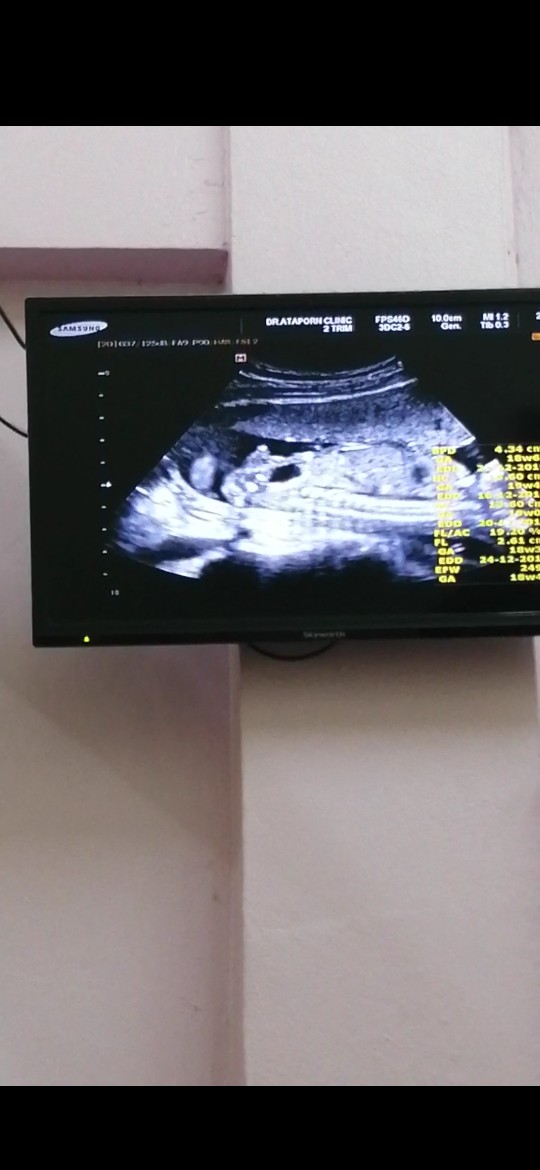

ท้อง5เดือนกว่า

ซาว์ดทั้ง2รอบคุณหมอบอกได้ลูกสาวค่ะ. แม่แอบดีใจมากๆ. คลอดเดือนธันวาคม. แม่ๆบ้านไหนกำหนดคลอดเดือนธันวาบ้างค่ะ ได้ลูกเพศอะไรกัน